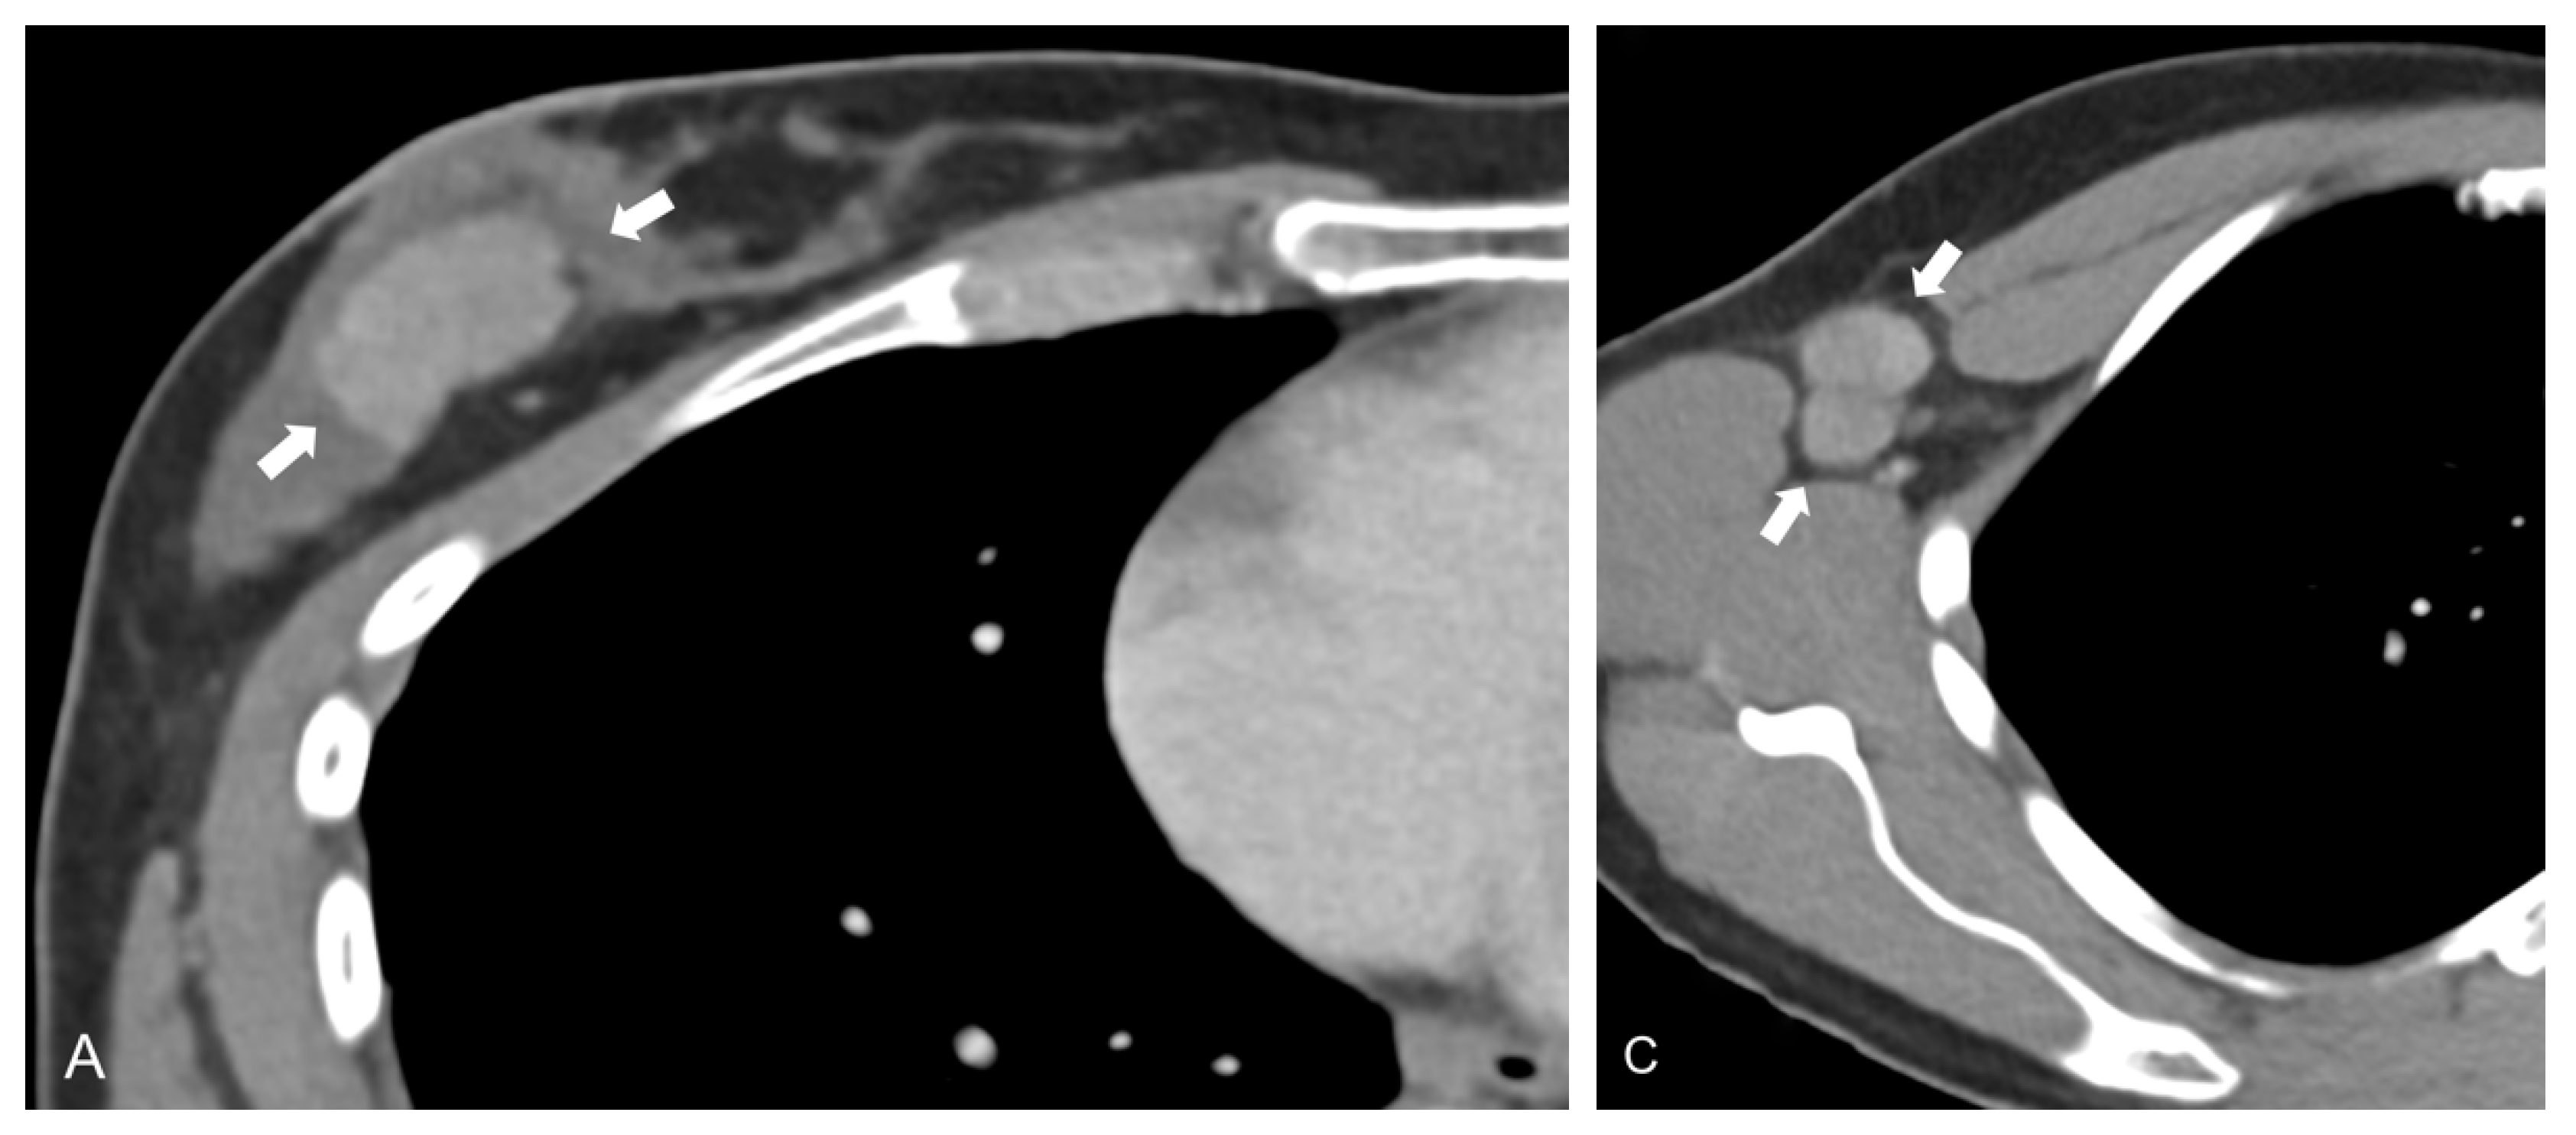

- Zhang, X.; Zheng, C.; Yang, Z.; Cheng, Z.; Deng, H.; Chen, M.; Duan, X.; Mao, J.; Shen, J. Axillary Sentinel Lymph Nodes in Breast Cancer: Quantitative Evaluation at Dual-Energy CT. Radiology 2018, 289, 337–346. [Google Scholar] [CrossRef]

- Zhou, Y.; Su, G.Y.; Hu, H.; Ge, Y.Q.; Si, Y.; Shen, M.P.; Xu, X.Q.; Wu, F.Y. Radiomics analysis of dual-energy CT-derived iodine maps for diagnosing metastatic cervical lymph nodes in patients with papillary thyroid cancer. Eur. Radiol. 2020, 30, 6251–6262. [Google Scholar] [CrossRef] [PubMed]